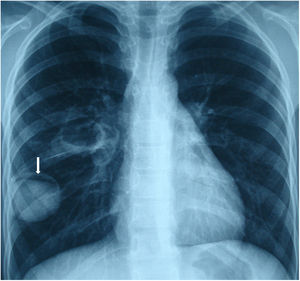

A 17 years old male presented with cough. Posteroanterior and lateraly direct radiography showed cavitary lesion in the middle zone and “moonsign” in the lower zone of the right lung (Figs. 1 and 2). The patient underwent right thoracotomy. Cystotomy and capitonnage was performed to hydatid cyst.

Fig. 1.

Moon sign is seen on the posteroanterior chest X-ray (arrow).

Radiologically, there are many radiological signs associated with the hydatid cyst.1,2 Moon sign is seen when air enters between the pericyst and endocyst. This finding indicates that the hydatid cyst will rupture. Radiological findings have an important role in the diagnosis of pulmonary hydatid cyst.